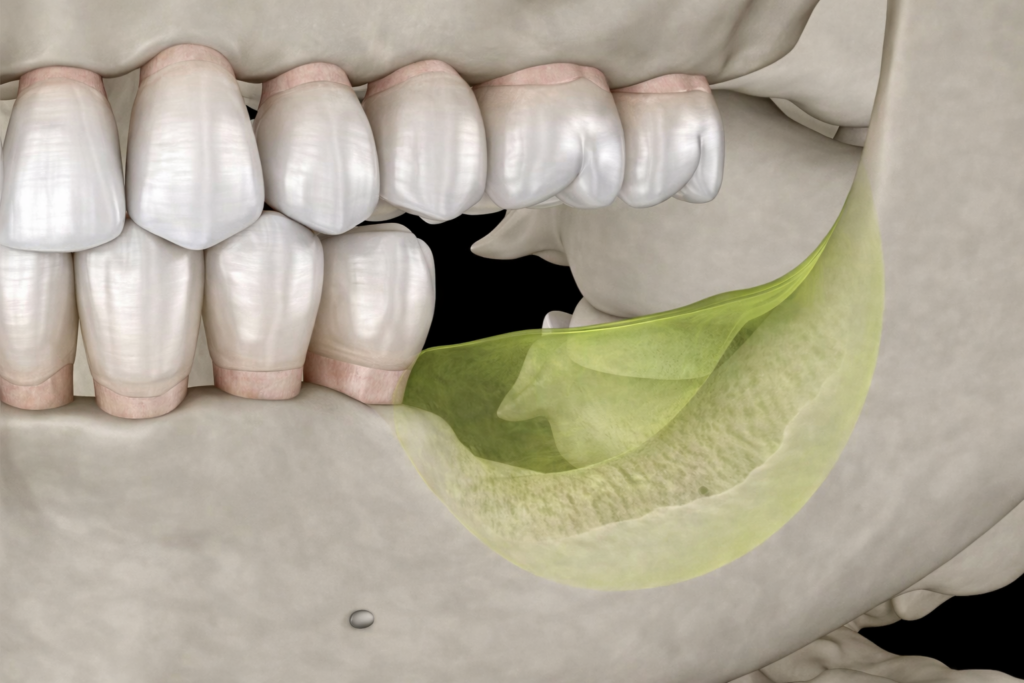

サイナスリフトとは

サイナスリフトとは、インプラントに必要な骨の高さや厚みが不足している上顎(上顎洞と呼ばれる空洞の上)で行う骨造成手術です。

歯肉を切開し、上顎洞に骨補填材を注入して骨の厚みを増すことで、インプラントを安全に埋め込む土台を作ります。

特に、顎骨の高さが5mm以下など、重度の骨不足の方に適用される専門性の高い手術です。体への負担は大きくなりますが、他院で難しいとされた症例にも対応し、インプラント治療を可能にします。

サイナスリフトの治療の流れ

サイナスリフトは、まずCT画像で上顎の骨不足を詳細に診断・計画します。手術は局所麻酔下で行い、上顎の頬側から歯茎を切開し、骨に慎重に小さな窓を開けます。その窓からシュナイダー膜(上顎洞の粘膜)を破らないよう剥がして持ち上げ、できた空洞部分に骨補填材を奥から注入し、骨の厚みを造成します。骨補填材を入れた後に窓を塞ぎ、歯茎を縫合して完了です。この手術は多くの場合、インプラント体の埋入と同時に行われ、その後、所定の期間を経て骨が形成・結合したことを確認してから、人工歯の装着へと進みます。